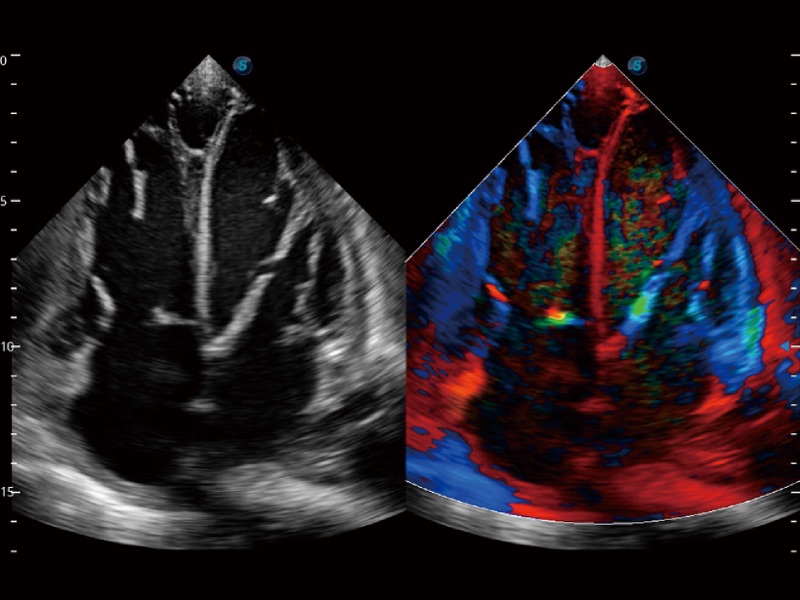

• 心血管应用

• 负荷超声心动图

支持运动和药物负荷协议、多心动周期存储选择,为临床观察心肌负荷状态下的室壁节段运动、评估心肌缺血状态提供更多的解决方案。

• 心肌定量分析 MQA

通过心肌识别技术和二维斑点追踪技术相结合,计算心肌各节段的应变应变率、速度、位移并以曲线图显示,实现整体或者局部心肌定量分析。同时可呈现牛眼图直观和准确诊断心肌的运动情况。

临床图